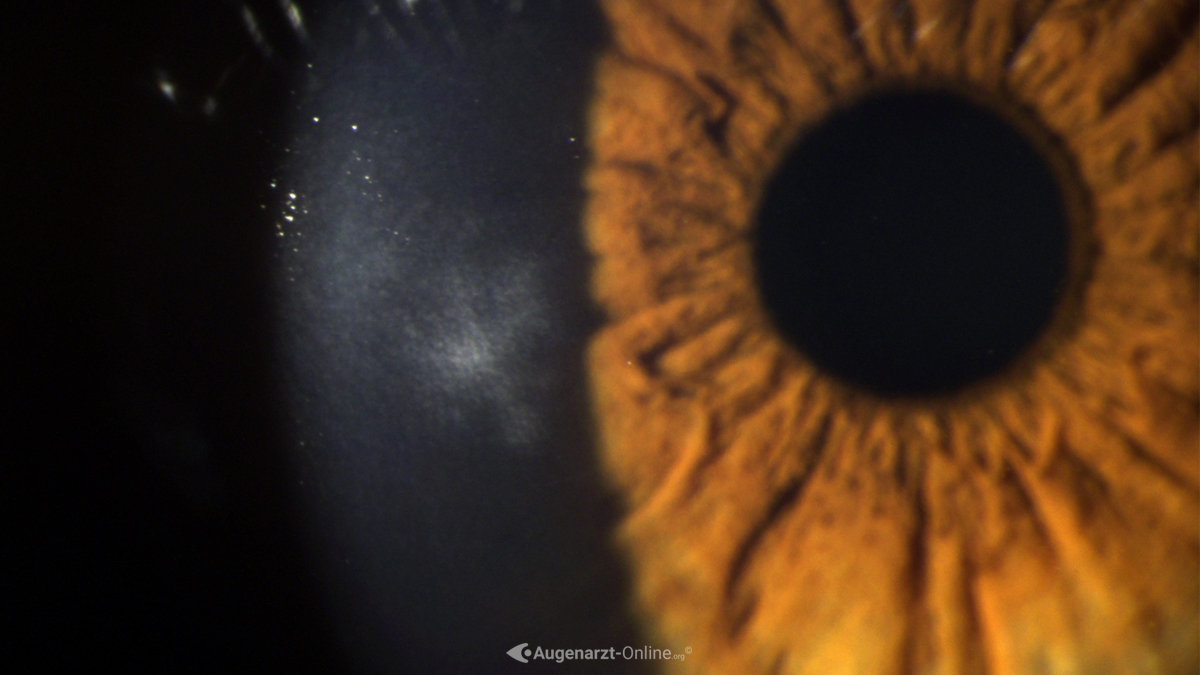

From www.augenarzt-online.org

Keratitis dentritica Atlas der Augenheilkunde Does Keratitis Go Away first, anyone with symptoms of keratitis who wears contacts should remove them and keep them off until the condition has gone away. Treatment for keratitis depends on the. if you get keratitis as a result of an injury, it will usually go away on its own as your eye recovers. If you have eye redness or other. . Does Keratitis Go Away.